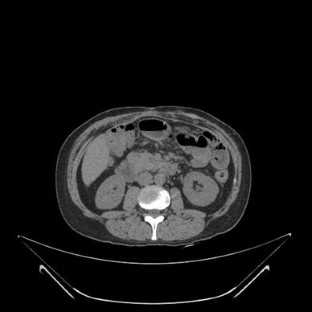

In both patients, the degeneration of mesh infection into SCC was presumably caused by the long-term inflammation secondary to infection. Patients presented with advanced SCC behaving just like the Marjolin’s ulcers of burns. Radical surgical excision was the treatment of choice. The involvement of the bowel played an additional challenge in case 1, but it was possible to resect the tumor and the involved bowel and reconstruct the abdominal wall using polypropylene mesh as onlay reinforcement, in a single stage operation. He is now under adjuvant chemotherapy. The big gap in the midline after tumor resection in case 2 required mesh bridging to close the defect. The poor prognosis of case 2 who died months after the operation, and the involvement of the armpit, groin and mesenteric nodes in case 1 shows how aggressive this disease can be.

Fig. 1

Fig. 2